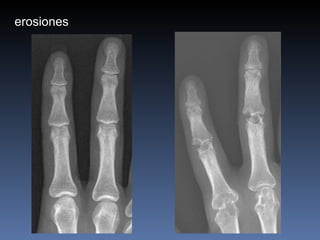

erosiones

Artritis Reumatoidea Muneca, MCFs, IFPs IFDs respetadas simetrica osteopenia Erosiones marginales Estrechez del espacio articular Edema fusiforme de tejidos blandos subluxaciones

Artritis Reumatoidea Muneca,MCFs, IFPs IFDs respetadas simetrica osteopenia Erosiones marginales Estrechez del espacio articular Edema fusiforme de tejidos blandos subluxaciones